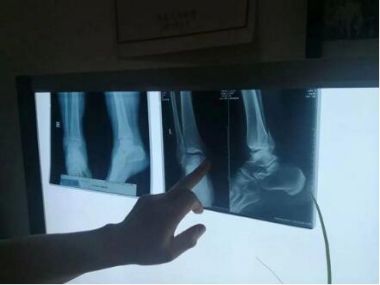

勾宪伟,男,15岁,沛县杨屯镇甘庄村。随父母在上海打工,玩耍时不慎摔伤右膝关节。即在上海中医院就医,x光片显示右胫骨髁间隆突撕脱性且移位骨折,院方的处理方案,必须动手术,用螺丝钉在内部固定,石膏外固定。由于手术费用过高,当时,家庭条件差难以承受,于是决定回老家沛县治疗。

生院长仔细看过x片后说:“这种骨折很好治。”听到生院长对儿子的骨折治疗十分有把握,担心害怕的父母才放下了心。

于是,生院长对骨伤开始进行诊断治疗:让患者平躺在治疗床上,要助手按住两腋下,并告知按得力度和角度,生院长用一只手握住患者踝关节上,另一只手扶着膝盖,连做两次伸曲膝关节的动作,手到骨正,随后外敷祖传正骨膏药,叮嘱患者可以做自由伸曲活动。原本不动就疼痛难忍,现通过生大夫正骨术后不仅不疼还可以伸曲自如,高兴的父母连连称赞生大夫神奇的正骨技术。